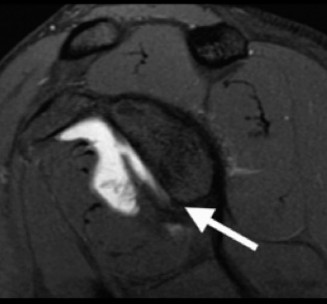

The correct answer is (A). In a young patient, the most likely injury associated with a glenohumeral dislocation is a labral tear (see Fig. 2–31). In an older patient, >40 years old, a rotator cuff tear is more likely. Other possible associated injuries include:

Figure 2–31 MRA demonstrating an anterior labral tear.

These all are less common than a labral tear. Each of these injuries need to be identified and treated appropriately at the time of surgery to ensure a satisfactory outcome.